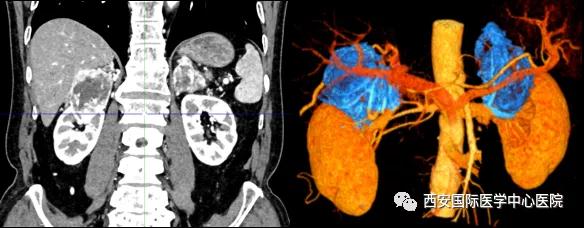

7月15日,西安國(guó)際醫(yī)學(xué)中心醫(yī)院泌尿外科楊增悅教授團(tuán)隊(duì)成功完成“機(jī)器人輔助根治性右腎、右腎上腺部分切除 左腎上腺切除 腎門淋巴結(jié)清掃術(shù)”。此臺(tái)手術(shù)涉及三個(gè)器官:右腎切除、右側(cè)腎上腺轉(zhuǎn)移瘤切除(保留部分正常腎上腺組織)、左腎上腺切除,并且清掃了腎門淋巴結(jié)。

今年七十五歲的患者,來(lái)自陜西省商洛市,四月前因腰背部疼痛就診于當(dāng)?shù)蒯t(yī)院,行CT檢查發(fā)現(xiàn)“右腎、雙側(cè)腎上腺占位,前縱膈淋巴結(jié)腫大,雙肺多發(fā)結(jié)節(jié)、胸椎骨質(zhì)破壞,考慮轉(zhuǎn)移瘤”。為進(jìn)一步診斷治療,患者的兒子帶他來(lái)到西安某三甲醫(yī)院,查泌尿系CT提示“右腎占位性病變,多考慮腎癌,雙側(cè)腎上腺多發(fā)轉(zhuǎn)移灶,腹膜后多發(fā)腫大淋巴結(jié)”;行穿刺活檢提示“腎透明細(xì)胞癌”;并給予患者口服靶向藥物的治療方案。

患者一家慕名前來(lái)到西安國(guó)際醫(yī)學(xué)中心醫(yī)院找到楊增悅教授。楊增悅教授仔細(xì)看完患者的之前的影像學(xué)及病理資料后,診斷為:右腎透明細(xì)胞癌(T4N1M1);并安排他住院。而后,主管醫(yī)生及時(shí)為他完善了術(shù)前檢查及評(píng)估。7月15日,在麻醉手術(shù)中心柴偉主任、王彬榮副主任、李娟護(hù)士長(zhǎng)、李瑞剛護(hù)士長(zhǎng)及全體麻醉手術(shù)中心團(tuán)隊(duì)的有力保障下,成功完成了這臺(tái)“大”手術(shù)。

手術(shù)由楊增悅教授主持,舒濤主治醫(yī)師、王東主治醫(yī)師主刀,黃怡醫(yī)師、王平醫(yī)師協(xié)助完成。由于第四代達(dá)芬奇機(jī)器人更加靈活和精準(zhǔn)的特性,手術(shù)全程順利,尤其是完全精準(zhǔn)的“解鎖”了右腎動(dòng)脈和右腎靜脈的數(shù)十根交互纏繞的分支血管。術(shù)后患者麻醉恢復(fù)后生命體征平穩(wěn),順利返回泌尿外科普通病區(qū)進(jìn)一步康復(fù)。